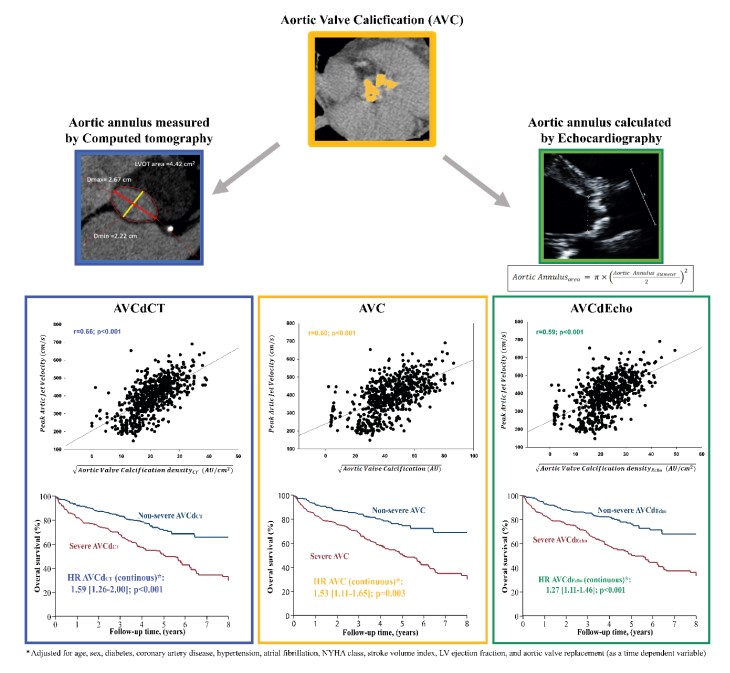

Aortic valve calcification divided by the area of the aortic annulus measured by #yesCT allows a better prediction of AS severity and outcome Labo Dr Clavel #AHAJournals Jiwon Kim, MD Kaz Negishi@Cardiologist/ Heart Mafia ahajrnls.org/4bva1hg